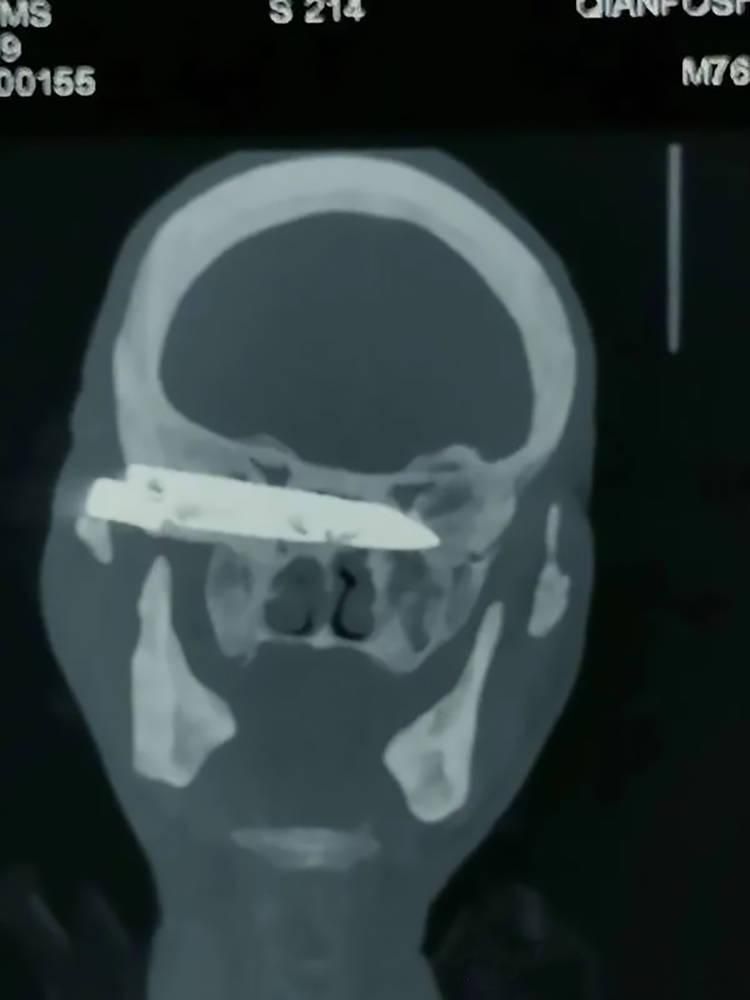

A 76-year-old man has survived a delicate surgery in which a four-inch-long rusty knife blade that got stuck inside his head after he had been stabbed 26 years ago was successfully removed, giving him respite now.

The ‘miracle man’ simply identified as Duorijie is a farmer from rural China from the rural county of Haiyan in China’s northwestern Qinghai Province.

Reports say he was stabbed in the head in 1994, during a violent attack, and had reportedly been living with a long knife blade stuck in his brain ever since.

CT scans and X-rays performed at the hospital of Shandong First Medical University in Jinan showed that the blade was located at the base of the patient’s skull, lodged against his eye socket and pressing against his optic nerve. Removing it would be difficult, but according to chief neurosurgeon Dr Liu Guangcun, it was “the only way to resolve the pensioner’s suffering once and for all.”